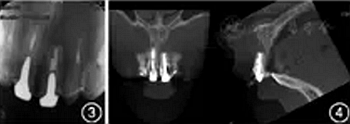

根尖X線片示根管中部以上可見高密度樁核影像,根充欠填,根尖有外吸收,根尖周低密度影。根管中上段無明顯顯影,結(jié)合臨床檢查判斷為纖維樁,根充欠填,根尖周未見明顯低密度影(圖3)。錐形束CT顯示根尖約4 mm×3 mm透影區(qū),根尖部唇側(cè)骨板缺損。根尖可見約1 mm×2 mm透影區(qū),唇側(cè)骨板完整(圖4)。根尖未見明顯低密度影。1年前根尖X線片顯示根充欠填,根尖低密度影,牙冠完整,根尖無異常(圖5)。

圖3 患者上前牙根尖X線片顯示,根尖外吸收,根尖周低密度影;根尖未見明顯低密度影;根充欠填,根尖周未見明顯低密度影